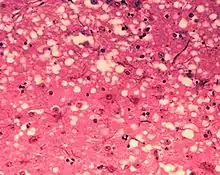

Microfotografía de la sustancia gris de un cerebro bovino afectado por BSE; se observa perfectamente la matriz fibrilar acidófila intercalada tras los somas neuronales que es la que constituye el neuropilo. Tinción Hematoxilina-Eosina.